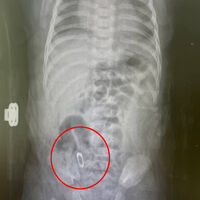

В Подмосковье из кишечника двухмесячного ребенка достали булавку. Об этом сообщает Telegram-канал «Разборчивым почерком».

По информации Telegram-канала, инцидент произошел в городе Люберцы. Двухмесячный ребенок поступил в областной центр материнства и детства, где врачи обнаружили в конечном отделе его тонкой кишки булавку. Отмечается, что она была закрыта и угроза травматизации стенки кишечника иголкой отсутствовала.

Хирурги приняли решение извлечь инородный предмет трансректально. В ходе малоинвазивного вмешательства врачи сместили булавку в сигмовидную кишку и успешно достали ее. Таким образом, медики помогли ей покинуть организм малолетнего естественным путем, сократив послеоперационную реабилитацию.